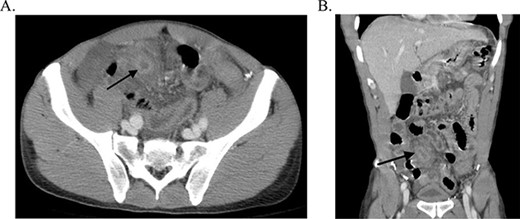

The patient was afebrile with stable vital signs. His abdomen was diffusely tender with greatest tenderness to palpation in the right lower quadrant as well as involuntary guarding, rebound tenderness and positive McBurney’s point. On admission, the patient had leukocytosis. CT abdomen/pelvis showed a thickened tubular structure in the right lower quadrant that was concerning for appendicitis (Fig. 1), with wall thickening of multiple small bowel and colonic loops possible secondary to peritonitis. The patient underwent an emergent laparoscopic appendectomy with lysis of adhesions.